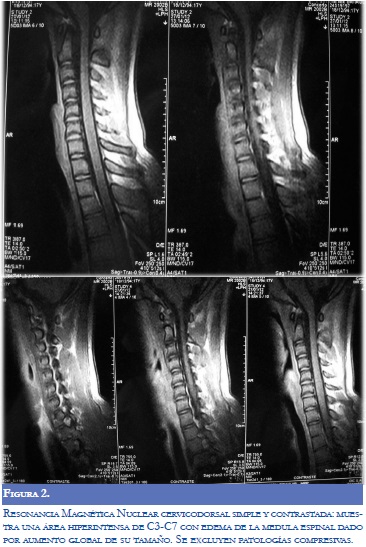

Ante la sospecha clínica de mielitis transversa, se solicitó resonancia magnética (RM) toracolumbar simple y contrastada. Se inició manejo con metilprednisolona con una dosis de 1 gr IV al día durante 3 días. Se ordenó RM cervico dorsal (Figura 2); y se inició aciclovir de 600 mg IV cada 8 horas.

Posterior al manejo con esteroides y aciclovir el paciente presentó mejoría significativa de su fuerza muscular y sensibilidad, por lo que se decidió dar salida luego de 19 días de manejo intrahospitalario. Al momento del egreso no tenía paraparesia, persistía leve disfunción sensitiva, sin retención urinaria, se ordenó aciclovir 800 mg VO cada 4 horas hasta completar 21 días de tratamiento.